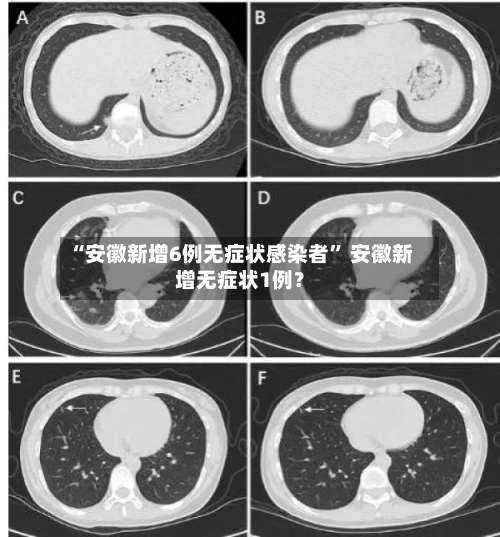

“安徽新增6例无症状感染者	” 安徽新增无症状1例?-第1张图片

“安徽新增6例无症状感染者” 安徽新增无症状1例?-第2张图片

“安徽新增6例无症状感染者” 安徽新增无症状1例?-第3张图片